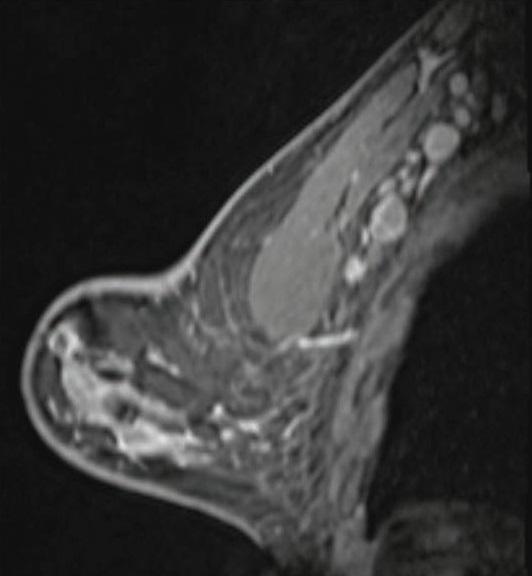

Shabnam Mortazavi of the University of California at Los Angeles reviewed electronic medical records to identify women with post-COVID-19 vaccination adenopathy found from December 2020 to February 2021. For mammography, Mortazavi considered a node abnormal when its size, shape, or density was deemed disproportionate to other axillary nodes (ipsilateral or contralateral). On ultrasound, she deemed a node abnormal based on subjective assessment for cortical abnormalities, including focal or diffuse thickening greater than 3 mm, as well as nodal prominence compared to the contralateral axilla (when available). For MRI, Mortazavi considered a node abnormal when asymmetric in size and/or number to the contralateral axilla.

Twenty-three women exhibited axillary adenopathy ipsilateral to the vaccinated arm on screening or diagnostic breast imaging, and according to Mortazavi, "13% were symptomatic (axillary lump with possible tenderness)." Meanwhile, the adenopathy was detected incidentally on screening breast imaging in 43% (mammography, 5; ultrasound, 2; both mammography and ultrasound, 1; high-risk screening MRI, 2) and on diagnostic imaging for other reasons in 43% (BI-RADS 3 follow-up for breast finding, 3; screening callback for other reason, 2; non-axillary breast pain or lump, 5). Noting that the median interval between the first vaccine dose and imaging showing the abnormal node was 9.5 days, Mortazavi's results counted a total of 57% of women with one abnormal node. BI-RADS 2 was assigned in one woman, BI-RADS 3 in 21 (ultrasound in 4-24 weeks), and BI-RADS 4 in one.